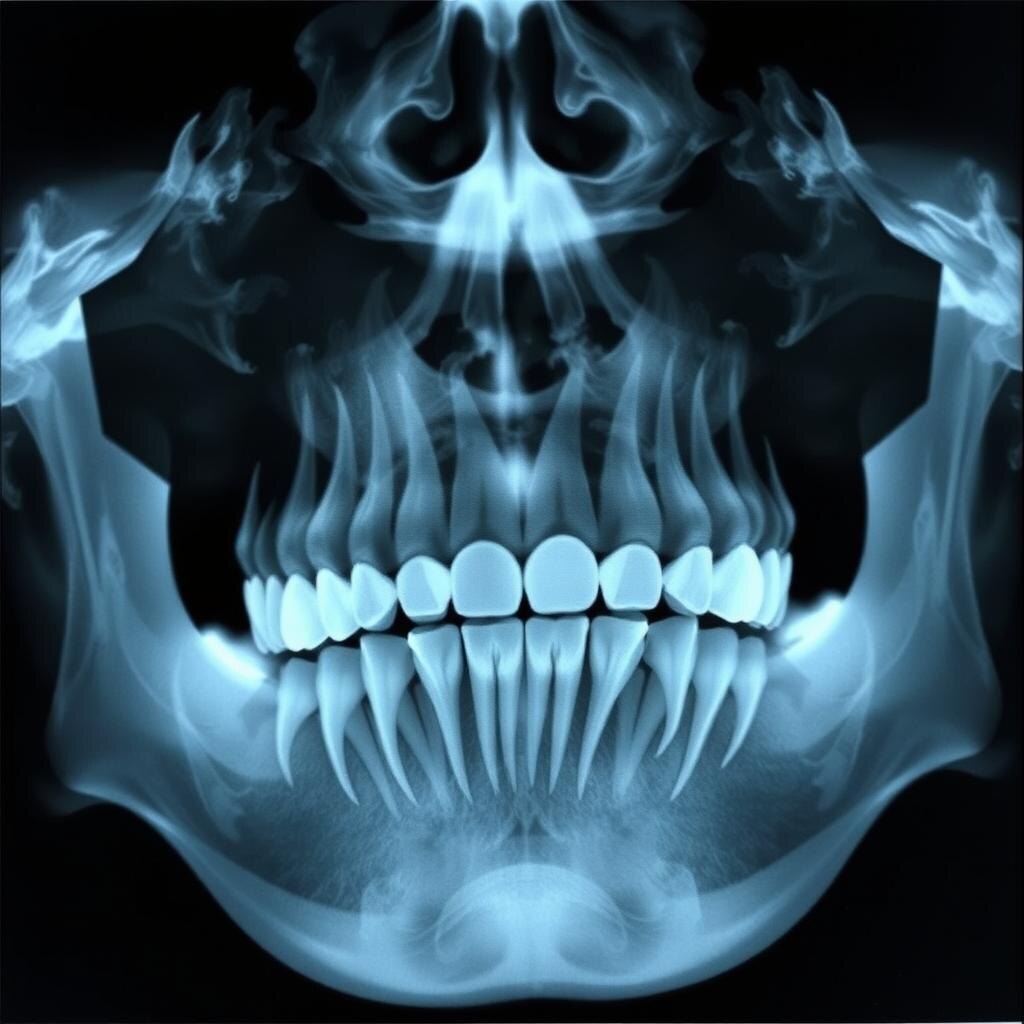

Стоматология — это область медицины, которая постоянно развивается, и сегодня появляются новые способы лечения зубов, которые могут сделать процедуры проще и комфортнее для пациентов. Одно из последних интересных исследований связано с использованием биотехнологий и регенеративной медицины для восстановления зубов.

Стволовые клетки — это особые клетки, которые могут превращаться в любые другие клетки нашего организма. Недавние исследования показывают, что стволовые клетки можно использовать для восстановления зубных тканей. Это значит, что в будущем, вместо того чтобы ставить пломбы или имплантаты, врачи смогут восстанавливать повреждённые зубы естественным образом.

Учёные научились использовать стволовые клетки, чтобы стимулировать рост новых тканей зуба, таких как дентин (это основная часть зуба) и эмаль (внешний защитный слой зуба). Если эти технологии станут доступны в стоматологических клиниках, можно будет лечить зубы так, чтобы они восстанавливались сами, без установки искусственных материалов.